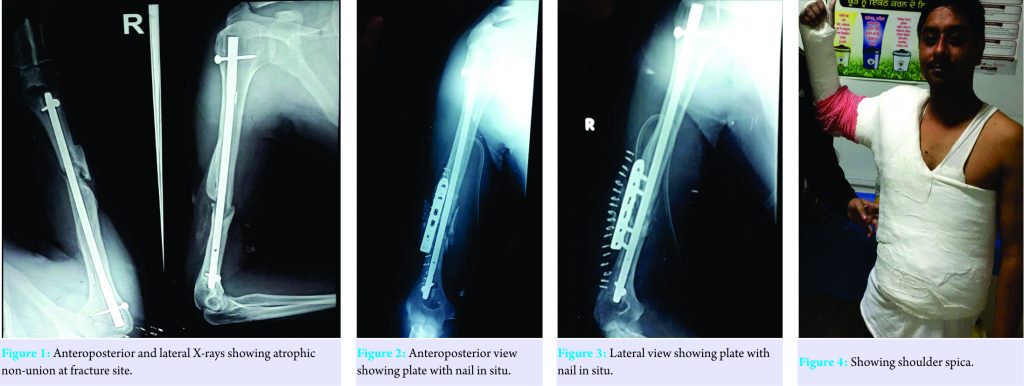

A 35-year-old young adult male presented to our department with pain over lower one-third of the right arm. Detail history taking revealed that the patient was a chronic smoker and alcoholic who sustained a compound fracture of the right shaft humerus 1 year back for which he underwent interlocking nailing at some private center. He further told us that the operating surgeon did iliac crest bone grafting 6 months after the initial surgery when no signs of union were evident. However, in spite of that, no signs of union were seen and he had persistent pain at fracture site when he used to perform household activities. He again went to the operating surgeon who referred the patient to our center. We got the anteroposterior and lateral X-rays done which revealed atrophic non-union at fracture site with one locking hole proximally and one distally (Fig. 1).

The nail seemed to be of appropriate diameter well seated in the medullary canal and removal of nail would have caused more damage to the rotator cuff. The patient was in a lot of mental trauma after the failed previous two surgeries, so he was counseled properly, and the decision was made to apply a locking compression plate (LCP) with nail in situ with iliac crest autogenous bone grafting. The patient being a chronic smoker and alcoholic was told that both smoking and alcohol cessations were mandatory before any definitive procedure and he agreed to that. After the preanesthetic checkup clearance, the patient was taken up in the theater; fracture site was opened posteriorly using triceps-splitting approach. As expected, there was rotational instability at the fracture site and no signs of callus formation were seen. The fracture margins were freshened till bleeding bone was visualized, fibrous tissue cleared, and locking compression with two monocortical holes on each side was applied along with bone graft harvested from iliac crest. Immediate post-operative anteroposterior and lateral radiograph were obtained (Fig. 2 and 3). After the stitches were removed and wound healed satisfactory, the patient was given shoulder spica to further ensure immobilization (Fig. 4). Shoulder spica was removed after 1 month and aggressive physiotherapy was started. Follow-up at the end of 6 months showed solid union at fracture site (Fig. 5) and excellent range of motion (Fig. 6a and b).